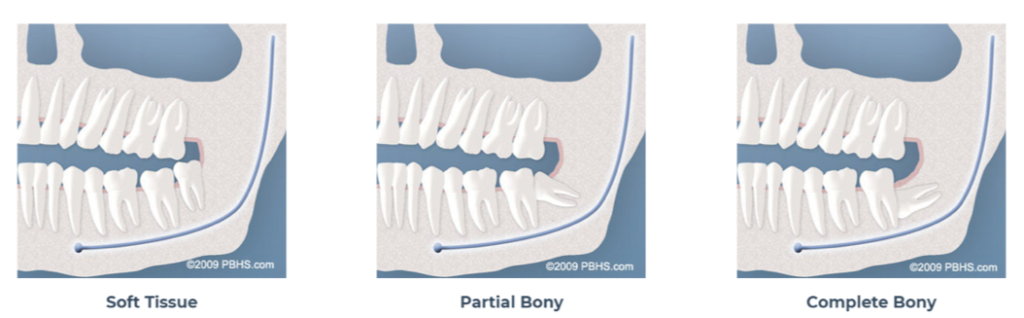

TYPES OF IMPACTIONS

- Soft Tissue Impaction: There is not enough room to allow the gum tissue to retract for adequate cleaning of the tooth.

- Partial Bony Impaction: There is enough space to allow the wisdom tooth to partially erupt. However, the tooth cannot function properly in the chewing process, and creates cleaning problems, among others.

- Complete Bony Impaction: There is NO space for the tooth to erupt. It remains embedded in the jawbone or if even partially visible requires complex surgical techniques for removal.The impacted wisdom tooth may also be in an unusual position and difficult to remove. This situation can also arise when the shape or size of the jawbone and other facial structures make removal of this tooth significantly more complex.